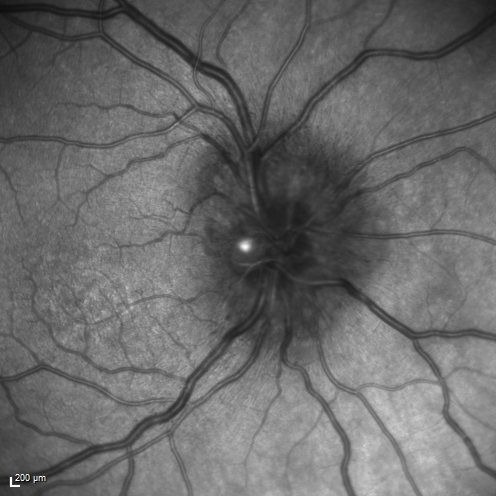

Syphillitic Optic Neuropathy and Maculopathy

46 year old woman with 2 weeks of vision loss OD.  VA 20/200 OD; 20/20 OS.  there are posterior vitreous cells on OCT in both eyes.  ICG, FAF, and FA show an abnormal macula OD.  VA improved to 20/30 within a month with treatment with PCN.